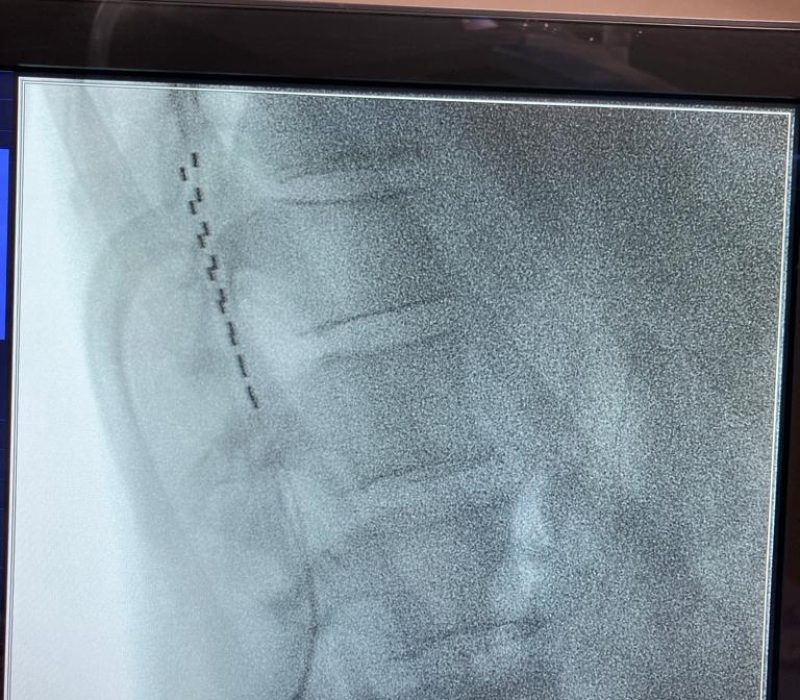

Los estimuladores de la médula espinal constan de cables delgados (los electrodos) y una pequeña batería similar a un marcapasos (el generador). Los electrodos se colocan entre la médula espinal y las vértebras (el espacio epidural) y el generador se coloca debajo de la piel, generalmente cerca de las nalgas o el abdomen.